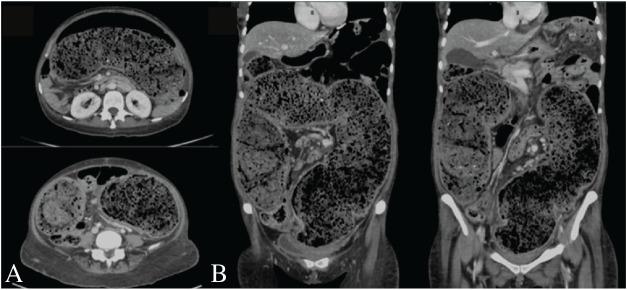

Antipsychotics have been associated with constipation, fecaloma, and stercoral colitis due to their anticholinergic properties. Benztropine, an antimuscarinic drug commonly used in psychiatric patients to alleviate extrapyramidal symptoms, may further decrease gastrointestinal mobility. Fecaloma and associated stercoral colitis are often diagnosed via imaging, typically a computed tomography scan of the abdomen. Management depends on the severity and generally ranges from conservative treatment to surgical options.

抗精神病药物因其抗胆碱能特性与便秘、粪石和粪性结肠炎有关。苯海索是一种常用于精神科患者以缓解锥体外系症状的抗毒蕈碱药物,可能会进一步降低胃肠蠕动。粪石及相关粪性结肠炎通常通过影像学检查诊断,典型的是腹部计算机断层扫描。治疗取决于严重程度,一般从保守治疗到手术选择。